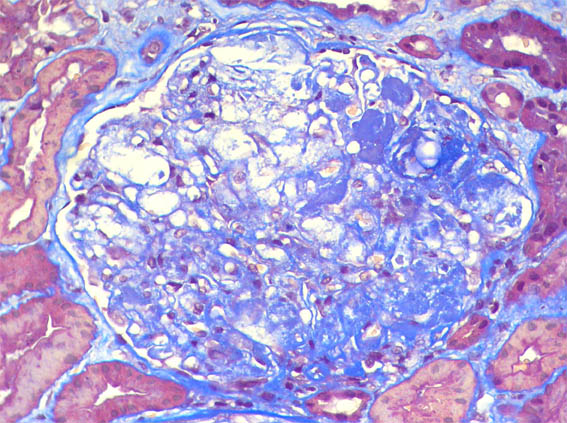

Figure 6. Masson's trichrome stain, X400.

Direct immunofluorescence for IgA, IgG, and C1q: negative. Kappa and lambda: focal and segmental traces. Fibronogen: negative.